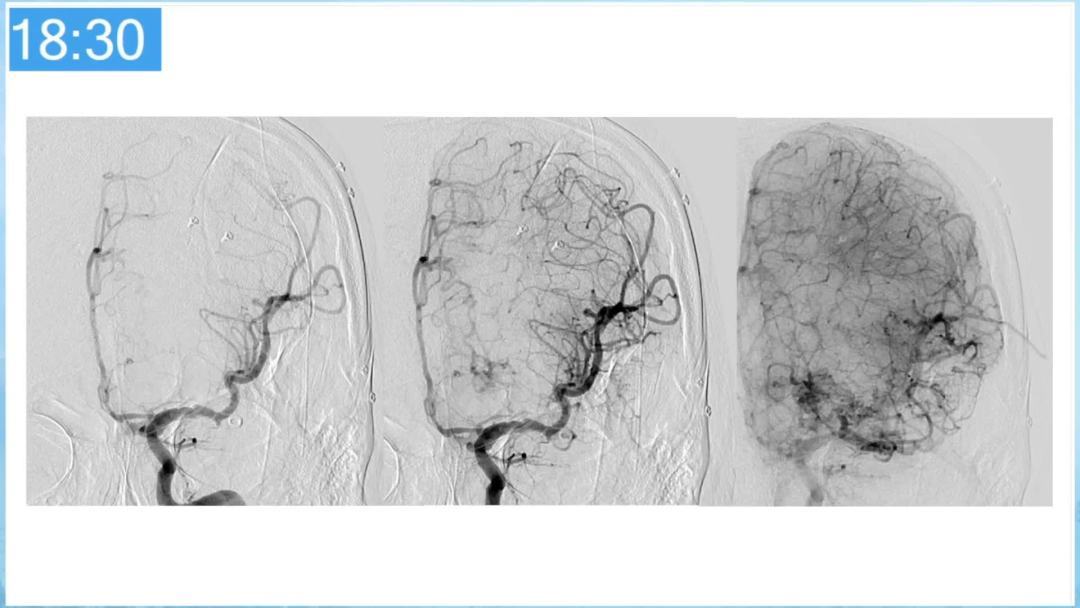

合理的复合平台下的综合治疗,针对每一个病变对应不同方法安全性分析,不预设、不排斥,每种技术发挥到最佳,互相保障。